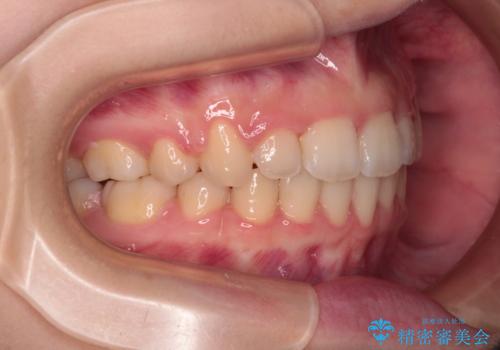

- 1年1ヶ月

舌の突出癖があり、前歯の移動量も多くなるため、治療期間は長くなると予想されましたが、13ヶ月という予定の半分程度の期間で終えることができました。